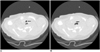

Fig. 10

Cine CT (A, inspiratory phase; B, expiratory phase) for diagnosis of tracheomalacia in 16-day-old female newborn with tracheoesophageal fistula, esophageal atresia and tetralogy of Fallot. Excessive expiratory collapsibility of trachea (arrows) is displayed on cine CT images. Distended proximal esophagus is also seen posterior to trachea.